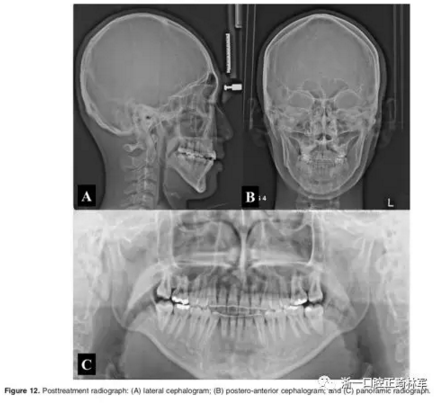

影像學(xué):頭顱側(cè)位片示:矢狀向和垂直向骨骼發(fā)生變化(ANB角,3°;SN-MP,51°);上頜切牙略前傾(U1-SN,106°),與下頜切牙一致(IMPA,75°);病人的面部輪廓得以保持。全景片示:由于牙齒萌出,上前牙區(qū)垂直向牙槽骨水平增加;雖然前牙牙根較彎曲,但其平行度仍可,且無明顯的牙根吸收。CBCT示:前牙唇側(cè)骨質(zhì)連續(xù)性改善,牙根唇側(cè)支持組織變好,牙槽骨高度、厚度均有增加,但轉(zhuǎn)矩的改變一定程度上導(dǎo)致了局部應(yīng)力的增大。

2年隨訪:咬合關(guān)系保持穩(wěn)定,無明顯復(fù)發(fā),下頜有一定晚期生長趨勢;前牙牙齦外形、牙冠高度無明顯變化;唇側(cè)牙槽骨高度、厚度均保持良好。